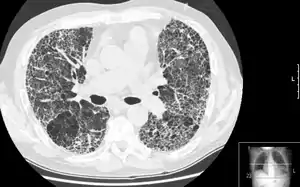

Компьютерная томография высокого разрешения (КТВР) лёгких — медицинское исследование, применяемое для диагностики и оценки интерстициальных заболеваний лёгких. Метод использует специальные параметры КТ-сканирования, позволяющие оценить состояние лёгочной ткани.

Поскольку КТВР применяется для оценки диффузных изменений легочной ткани, зона сканирования лёгких, как правило, составляет 10—40 мм. Полученные в результате исследования изображения демонстрируют характер структурных изменений в лёгких на основании данных на ограниченном участке (обычно 10 %).

В связи с тем, что зона сканирования при КТВР, как правило, меньше общей протяженности лёгких, метод нельзя использовать для диагностики рака лёгкого и другой локальной патологии. Также, в связи с высоким уровнем шума (связанным с тонкими срезами и высокоразрешающим алгоритмом реконструкции), невозможно достоверно визуализировать патологические изменения в мягких тканях средостения.